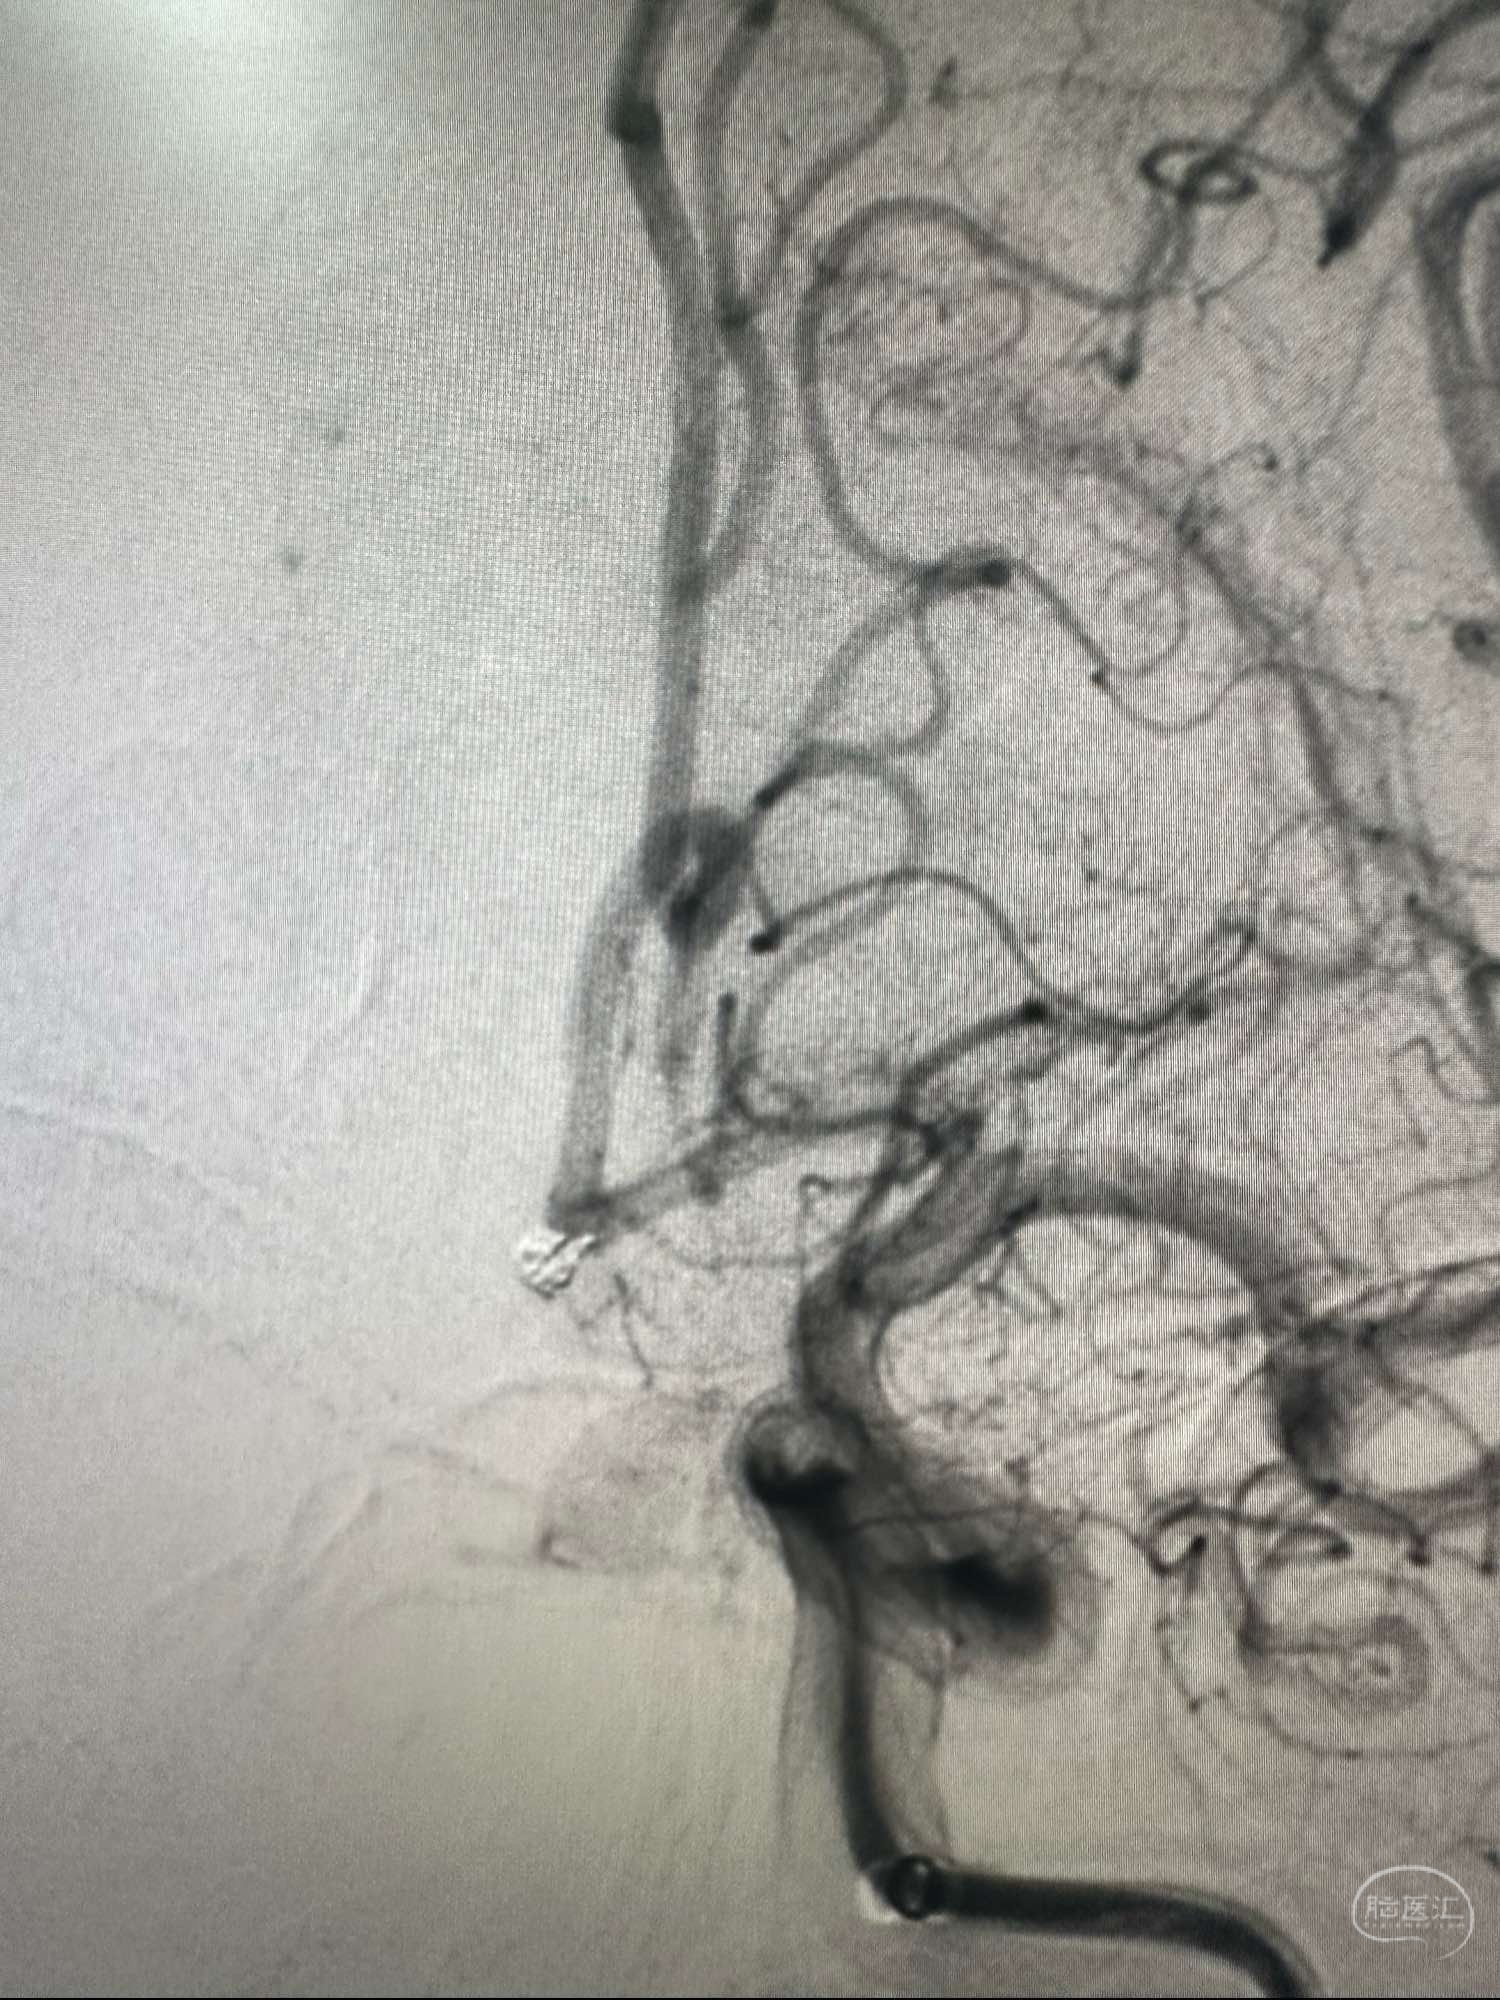

正位造影